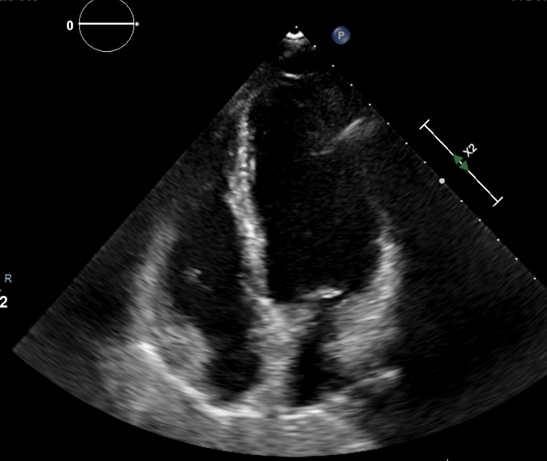

心臓超音波検査

心臓が対象の臓器です。

検査時間10~20分程度。

どんなことがわかる

心臓の機能や心筋梗塞、弁膜症、先天性心疾患の有無など

検査にあたって

上半身のみ検査着に着替えて検査を行います。

必要に応じて

弁疾患や心筋虚血の評価のため、運動や薬物により心臓に負荷をかけて行う場合もあります。

胃カメラのような細い管状の器械を飲み込んで、食道から心臓を描出する経食道超音波検査を行うこともあります。

写真 腹部超音波検査